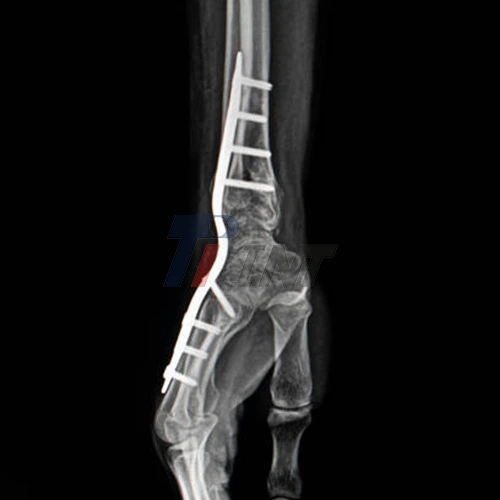

The application of a titanium plate for a broken wrist involves a surgical procedure where the plate is carefully affixed to the fractured bone using small screws. This technique, known as open reduction and internal fixation (ORIF), allows for precise alignment of the bone fragments and provides immediate stability to the injured wrist. In rehabilitation settings, this stability is crucial for initiating early mobilization and therapy, which are essential components of the recovery process.

When it comes to treating wrist fractures, titanium plates have emerged as a go-to solution for orthopedic surgeons and rehabilitation specialists. These innovative medical devices play a crucial role in stabilizing the fractured bones, allowing for proper alignment and facilitating the healing process. The use of a titanium plate for broken wrist offers several advantages over traditional treatment methods.

Titanium, known for its biocompatibility and strength-to-weight ratio, is an ideal material for orthopedic implants. When used in wrist fracture treatment, titanium plates provide robust support to the injured area while minimizing the risk of adverse reactions. This makes them particularly valuable in rehabilitation hospitals, where patients require reliable and effective treatment options to regain wrist function.